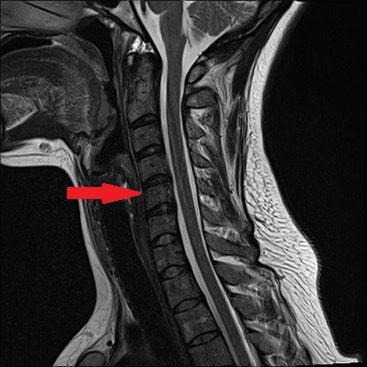

- МРТ или КТ для оценки состояния дисков, кровеносных сосудов, нервных стволов, мягких тканей;

Прицельно оценить состояние пораженного диска позволяет дискография. Определить локализацию и степень повреждения нервных путей помогают электрофизиологические исследования — вызванные потенциалы, электронейрография, электромиография.